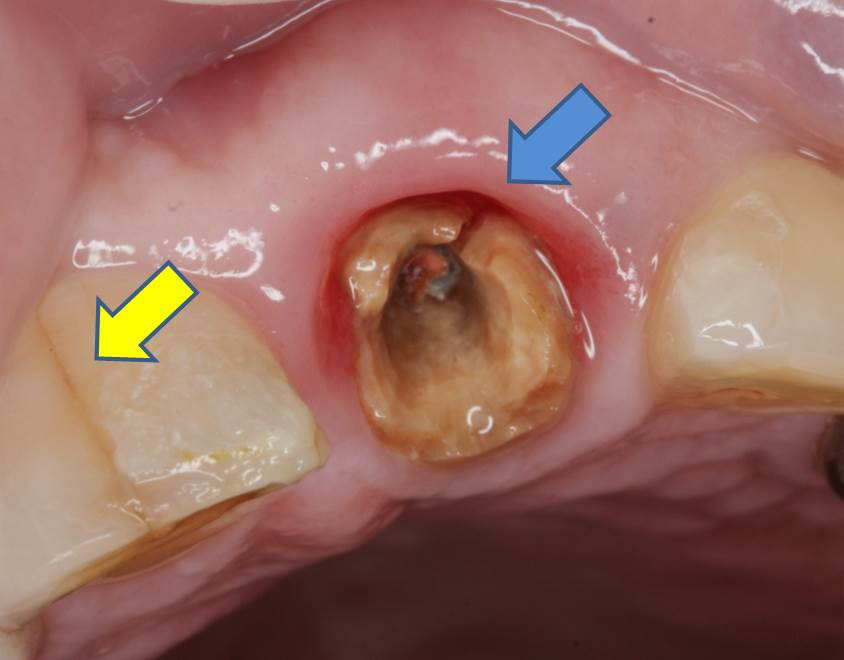

「以前に治療して装着した被せ物が外れたので、かかりつけ歯科医院にて診てもらい、再装着したが、どうも調子が悪い状態が続いている」とのことでした。画像は冠を外した状態の写真です。

青矢印部分に破折線が見られ、‟歯根縦破折”という状態でした。破折線は根尖まで及んでいた為、『歯根縦破折を伴う慢性根尖性歯周炎』の診断の元、残念ながら抜歯術の適応であることを説明し、同意の上、施術となりました。黄矢印部分は隣の歯の歯冠部分ですが、ここにもエナメル質のマイクロクラック(破折線)が見られます。この患者様のような破折線が見られる場合には「咬合力(嚙み合わせる力)」が非常に強く、噛みしめで歯を失っていく傾向にあるため、注意が必要です。